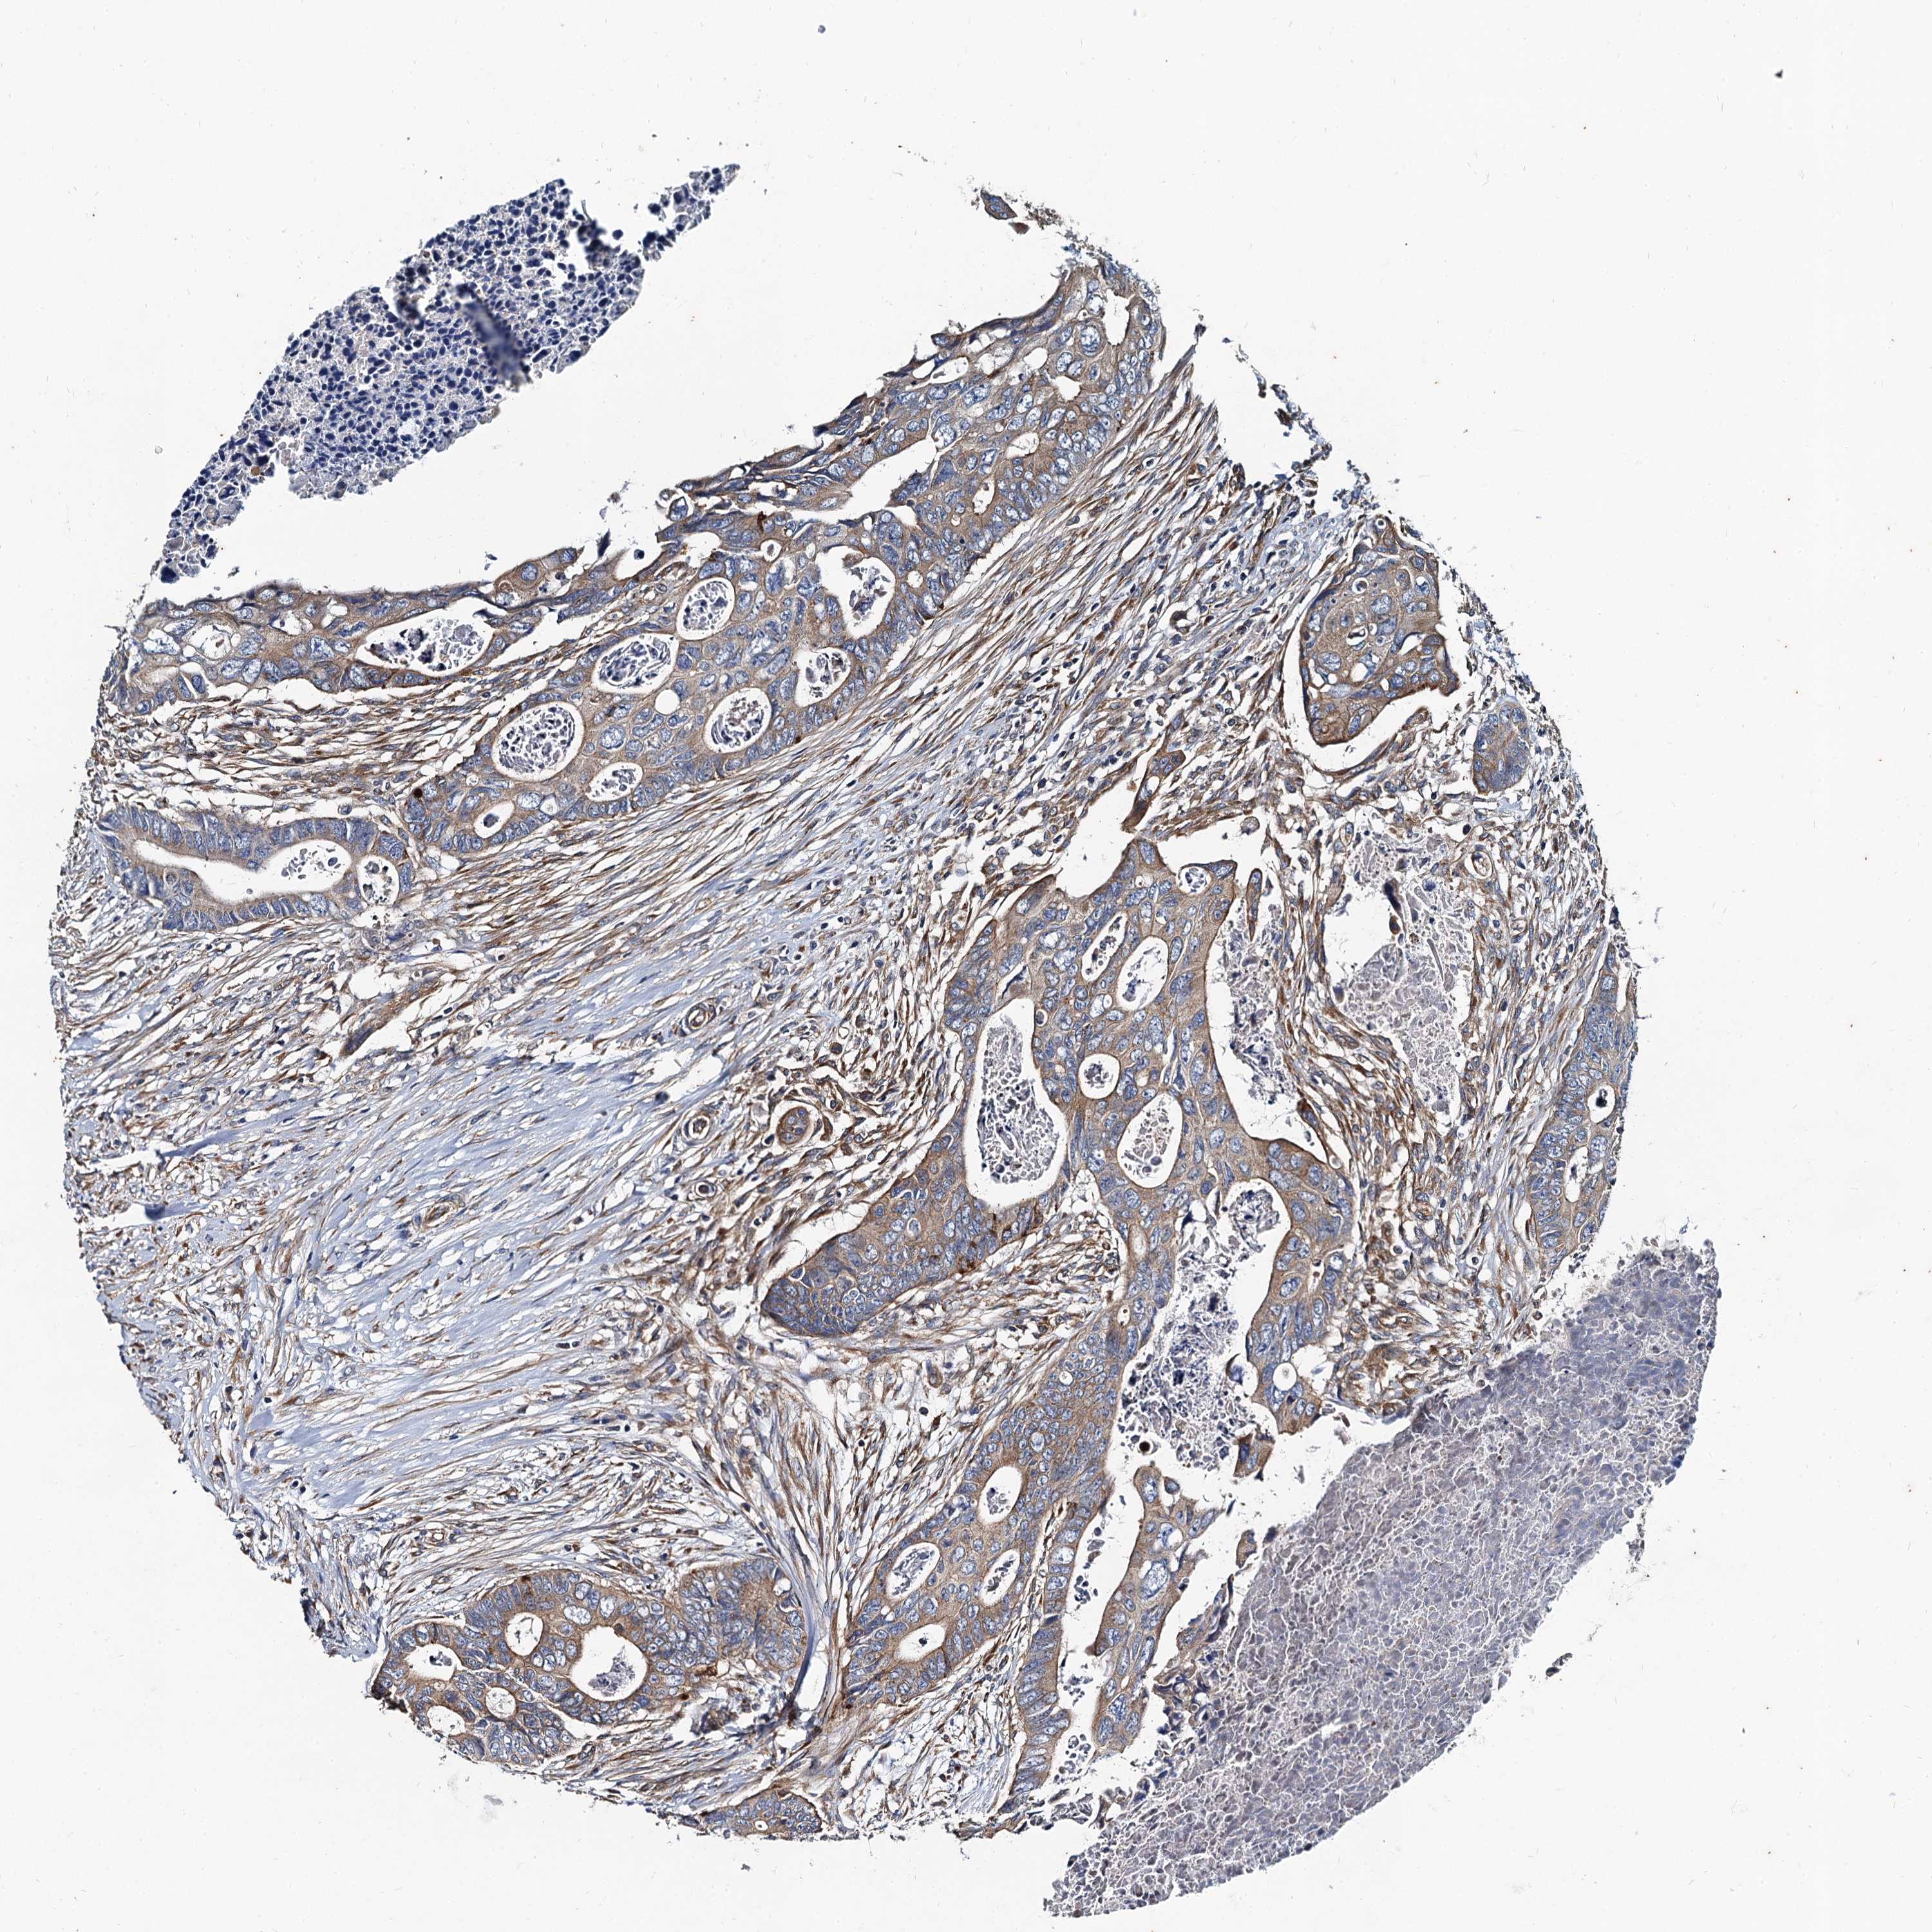

CANCER COLORECTAL CANCER Show tissue menu

COAD TCGA COAD VALIDATION READ TCGA READ VALIDATION PROTEIN COAD CPTAC PROTEIN EXPRESSION

ANTIBODIES

AND

VALIDATION